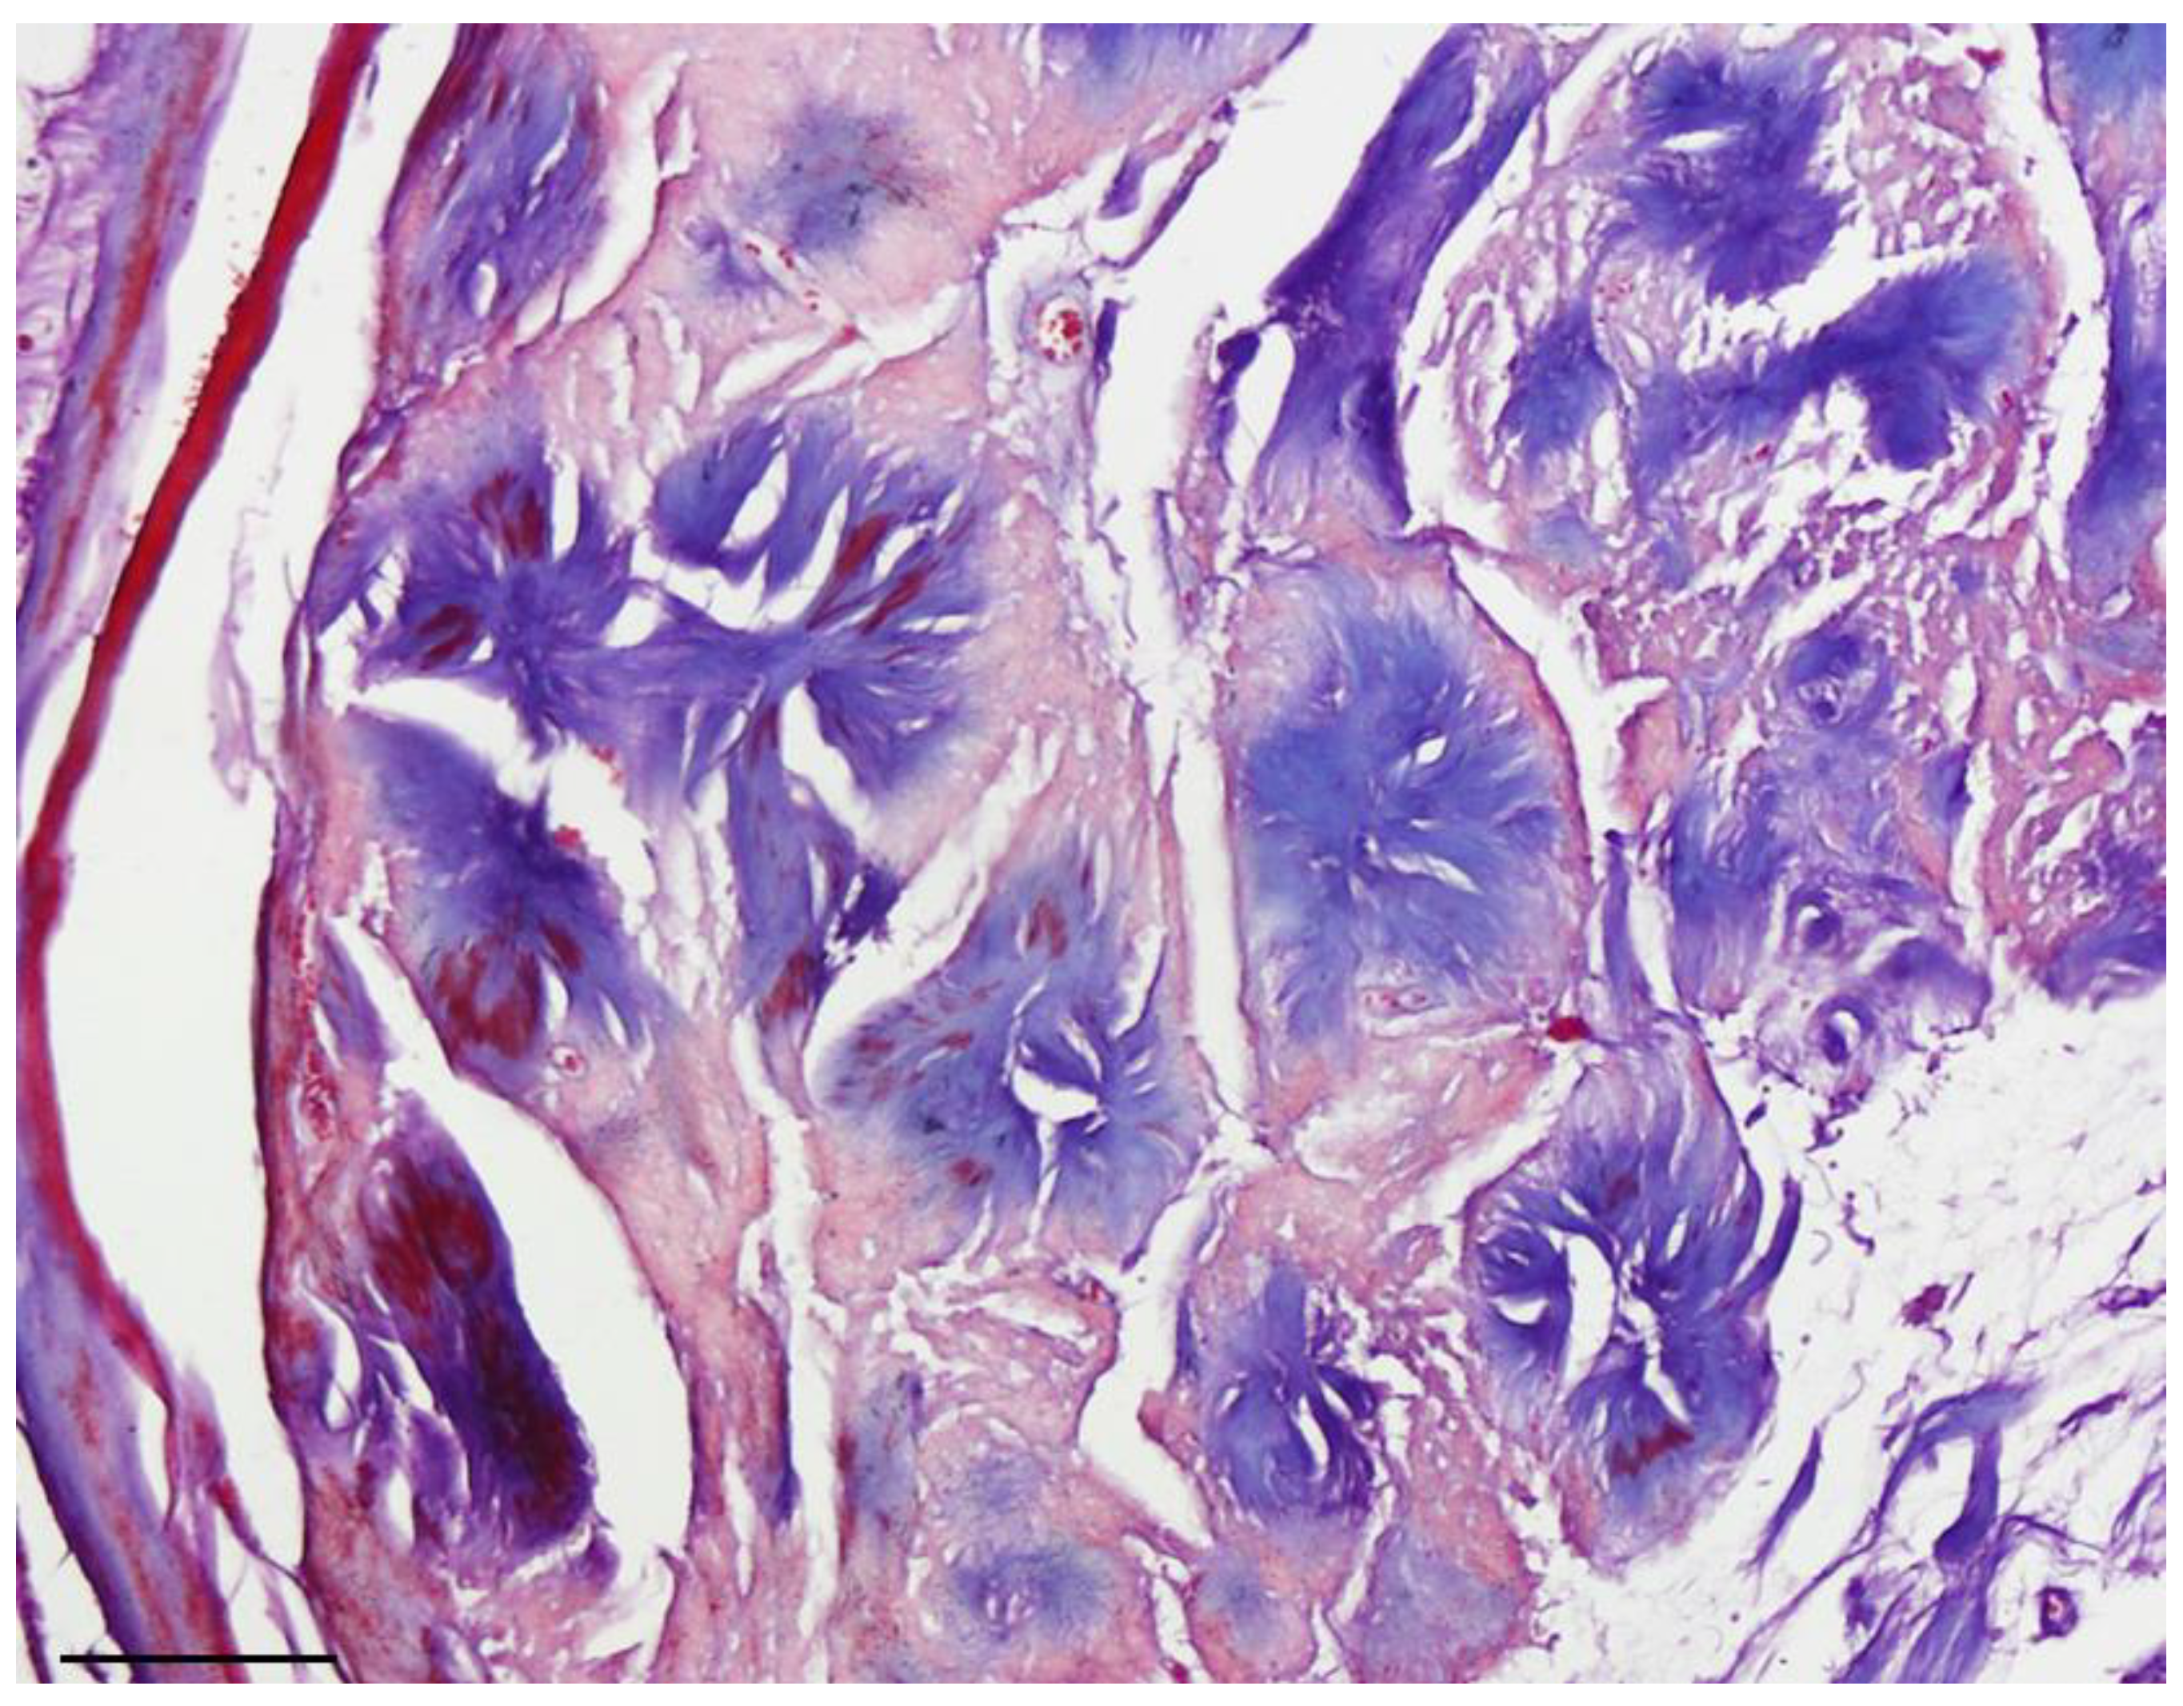

Figure 1. Neuroblastoma-like schwannoma: (A) Encapsulated neoplasm consists of small round cells around an eosinophilic core on H&E-stained tissue (10× objective lens, scale bar = 200 μm); (B). 40× small Schwann cells with scant cytoplasm and hyperchrome nuclei with a radial arrangement around a collagen core that formed giant rosettes on H&E-stained tissue (40× objective lens, scale ba r = 50 μm).

Histopathological investigation revealed a neoplastic tissue surrounded by a thin fibrous capsule and consisting of uniform small lymphocyte-like round cells with scant cytoplasm and small hyperchromatic nuclei. The cells were radially arranged around eosinophilic collagenous-core-forming giant rosettes. No cellular atypia, necrosis or mitosis was evident in this specimen. The classic pattern of schwannoma was notably absent in all representative sections.

Masson’s trichrome staining confirmed that the central core of the rosettes was composed of collagen fibers. Subsequent immunohistochemical study revealed diffuse expression of S100 protein (as the most commonly used marker to detect tumoral cells) [6] in the tumoral cells, confirming the Schwann cell origin of the tumor (Figure 1 and Figure 2). Additionally, staining for the neural markers showed focal positive expression for Neuron Specific Enolase (NSE) and negative for synaptophysin which confirmed our diagnosis (Figure 3 and Figure 4).

In our case, the histopathological investigation on Hematoxylin and Eosin (H&E) stained sections revealed a small cell tumor with the cellular characteristics of neuroblastoma described earlier, along with areas of conventional schwannoma. Moreover, no cellular atypia, necrosis or mitosis was evident in the specimen of our patient. These findings are consistent with the findings of previous neuroblastoma-like schwannoma case reports [16].